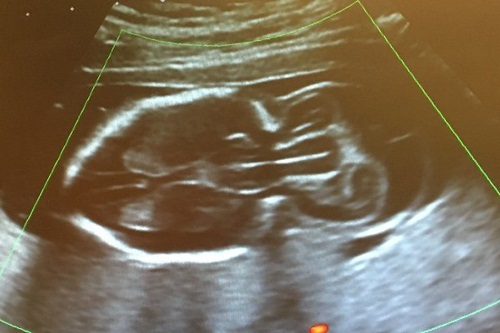

Hình ảnh siêu âm lúc thai nhi mới 20 tuần tuổi. |

Ngay từ khi thai nhi được 20 tuần tuổi, người ta đã quan sát được sự bất thường này và khiến thai kì của Analee trở thành một cơn ác mộng.